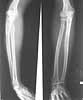

This patient,a middle aged malewas a diagnosed case of hypophosphatemic osteomalacia on treatment. Unfortunately he discontinued treatment since he was poor and also neutral phosphate was not available locally. He presented with pathological fracture of left femur and a failing neck of same femur.

We managed to get neutral phosphate, initiated medical treatment and did an antegrade SIGN nailing of left femur along with couple of screws to neck using miss a nail technique. He complained of pain of the right femur and both forearms. In OT these areas were screened using image intensifier and found that he has looser zones of all these with impending fractures. Yesterday we did a retrograde nailing of right femur usingSIGN nail. Both ulnas were stabilised usingLambrudini wires in a closed fashion. All fractures and looser zones were stabilised by closed surgery using image intensifier. It may be interesting to see the post of picture of both the hips in which one side shows an antegrade femoral SIGN nail and the other side shows a retrograde SIGN nail.